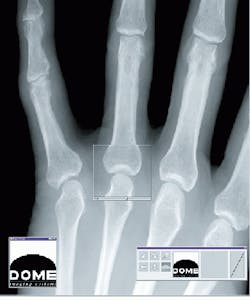

To meet these needs, VisiCom`s Vigra Sliver has a single-slot 6U VME bus video/graphics/audio board that provides video compression. At 1600 ¥ 1280-pixel resolution, its combination of audio and video capabilities are tailored for video conferencing, real-time video in a window, network video distribution, and video playback from a hard disk or CD-ROM.

FIGURE 3. VME-64 compatible interface connects the VisiCom Sliver from the VME bus to the board`s local 32-bit system bus. The VME bus provides an interface to x-ray data acquisition and to the host processor, dedicated image processor, and a LAN interface that provides communication with remote x-ray analysis stations.